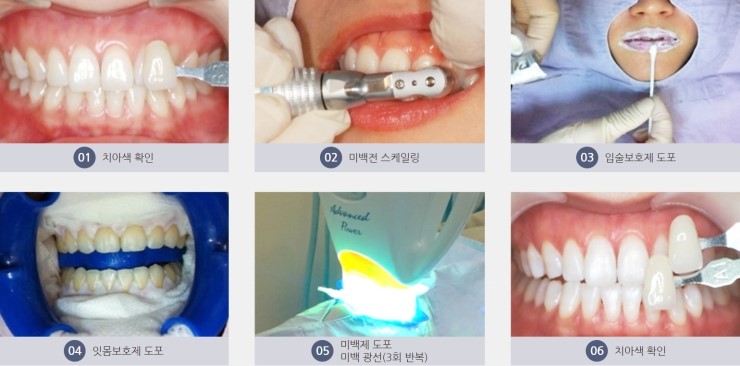

▣ 치과 미백 과정

1. 치아 색 확인

미백을 시작하기 전에

현재 색상을 확인하여

변색 상태를 파악합니다.

2. 미백 전 스케일링

미백 전, 치아 표면에 쌓인 치석과

플라그를 제거하는 스케일링을 진행합니다.

3. 입술 보호제 도포

미백제를 도포하기 전에

입술을 보호하기 위해 보호제를 바릅니다.

4. 잇몸 보호제 도포

약제가 잇몸에 닿지 않도록

잇몸 보호제를 도포하여 잇몸을 보호합니다.

5. 미백제 도포 및 미백 광선

치아에 미백제를 도포하고,

미백 광선을 사용하여

미백 약제의 효과를 활성화시킵니다.